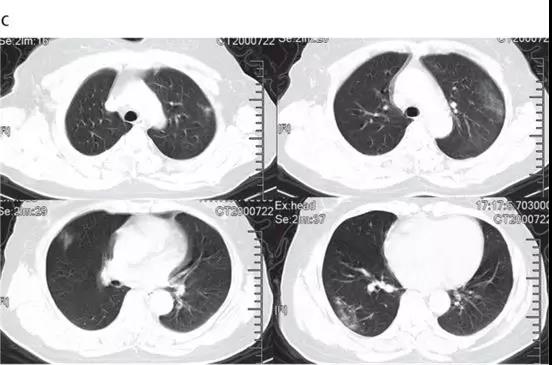

非ICU患者的代表性胸部CT检查表现为双侧毛玻璃样混浊和亚段实变(见下图)。